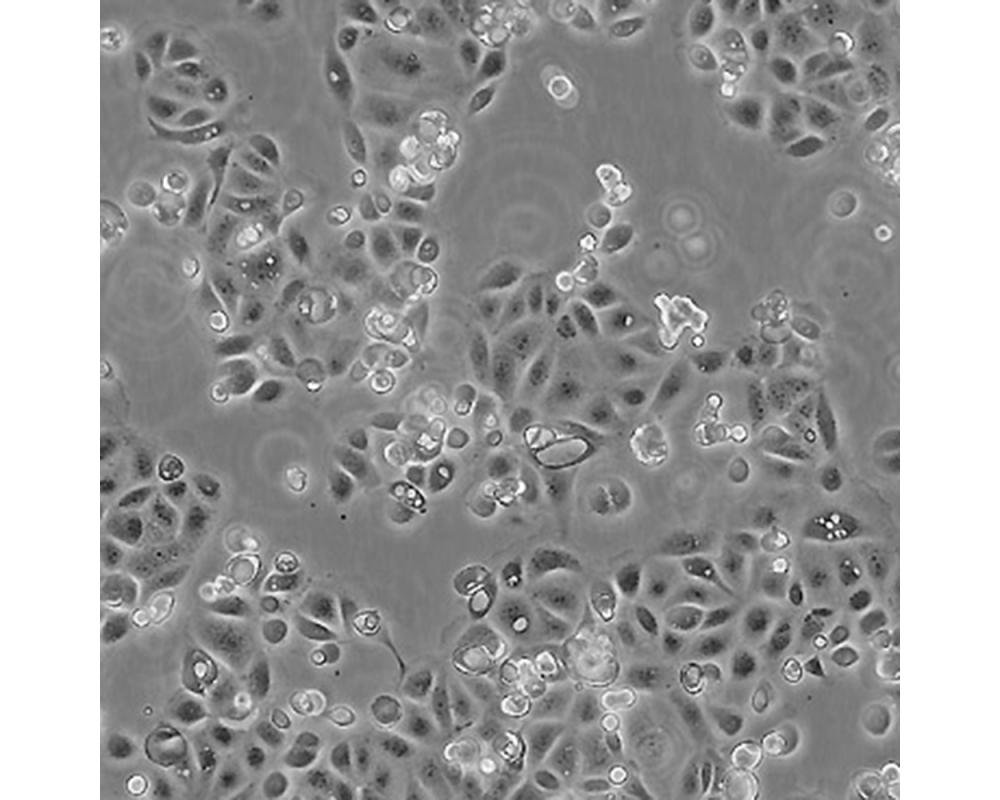

SW1990

中文名稱 人胰腺癌細(xì)胞

組織來(lái)源 胰腺癌;男性

生長(zhǎng)特性 貼壁

培養(yǎng)基 L15,90%;FBS,10%;雙抗。

培養(yǎng)條件 Atmosphere: Air, 95%; CO2, 5%。Temperature: 37℃